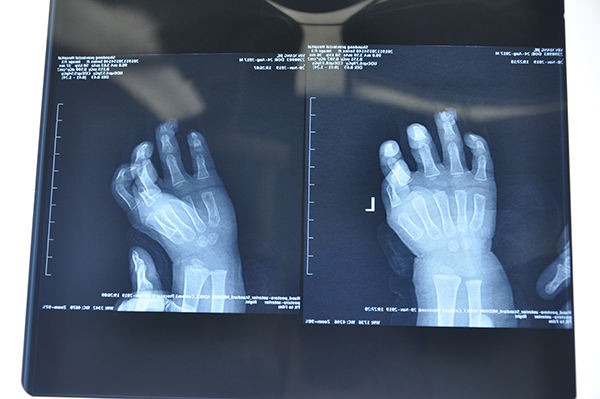

图片3.jpg

Figure 3术前X片